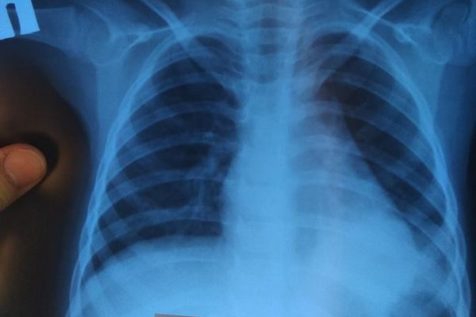

«Мне их некуда ложить!»: врачи Запорожья обеспокоены волной пневмонии

Врачи больниц уже не знают, в какие палаты доставлять граждан с пневмонией.

Стоит отметить, что в Пологовском районе, Запорожской области заболело уже 109 человек. И если до новогодних праздников фиксировались единичные случаи заболевания, то в январе люди начали болеть массово. Среди заболевших пневмонией — 64 ребенка.

На прошлой неделе, зафиксировано 18 случаев заболевания пневмонии в Пологах.

Медики напоминают, что при первых симптомах заболевания стоит срочно обратиться к врачам. Пневмония передается воздушно-капельным путем и является смертельным заболеванием. ВОЗ внесла данное заболевание в список самых распространенных причин смерти в мире.